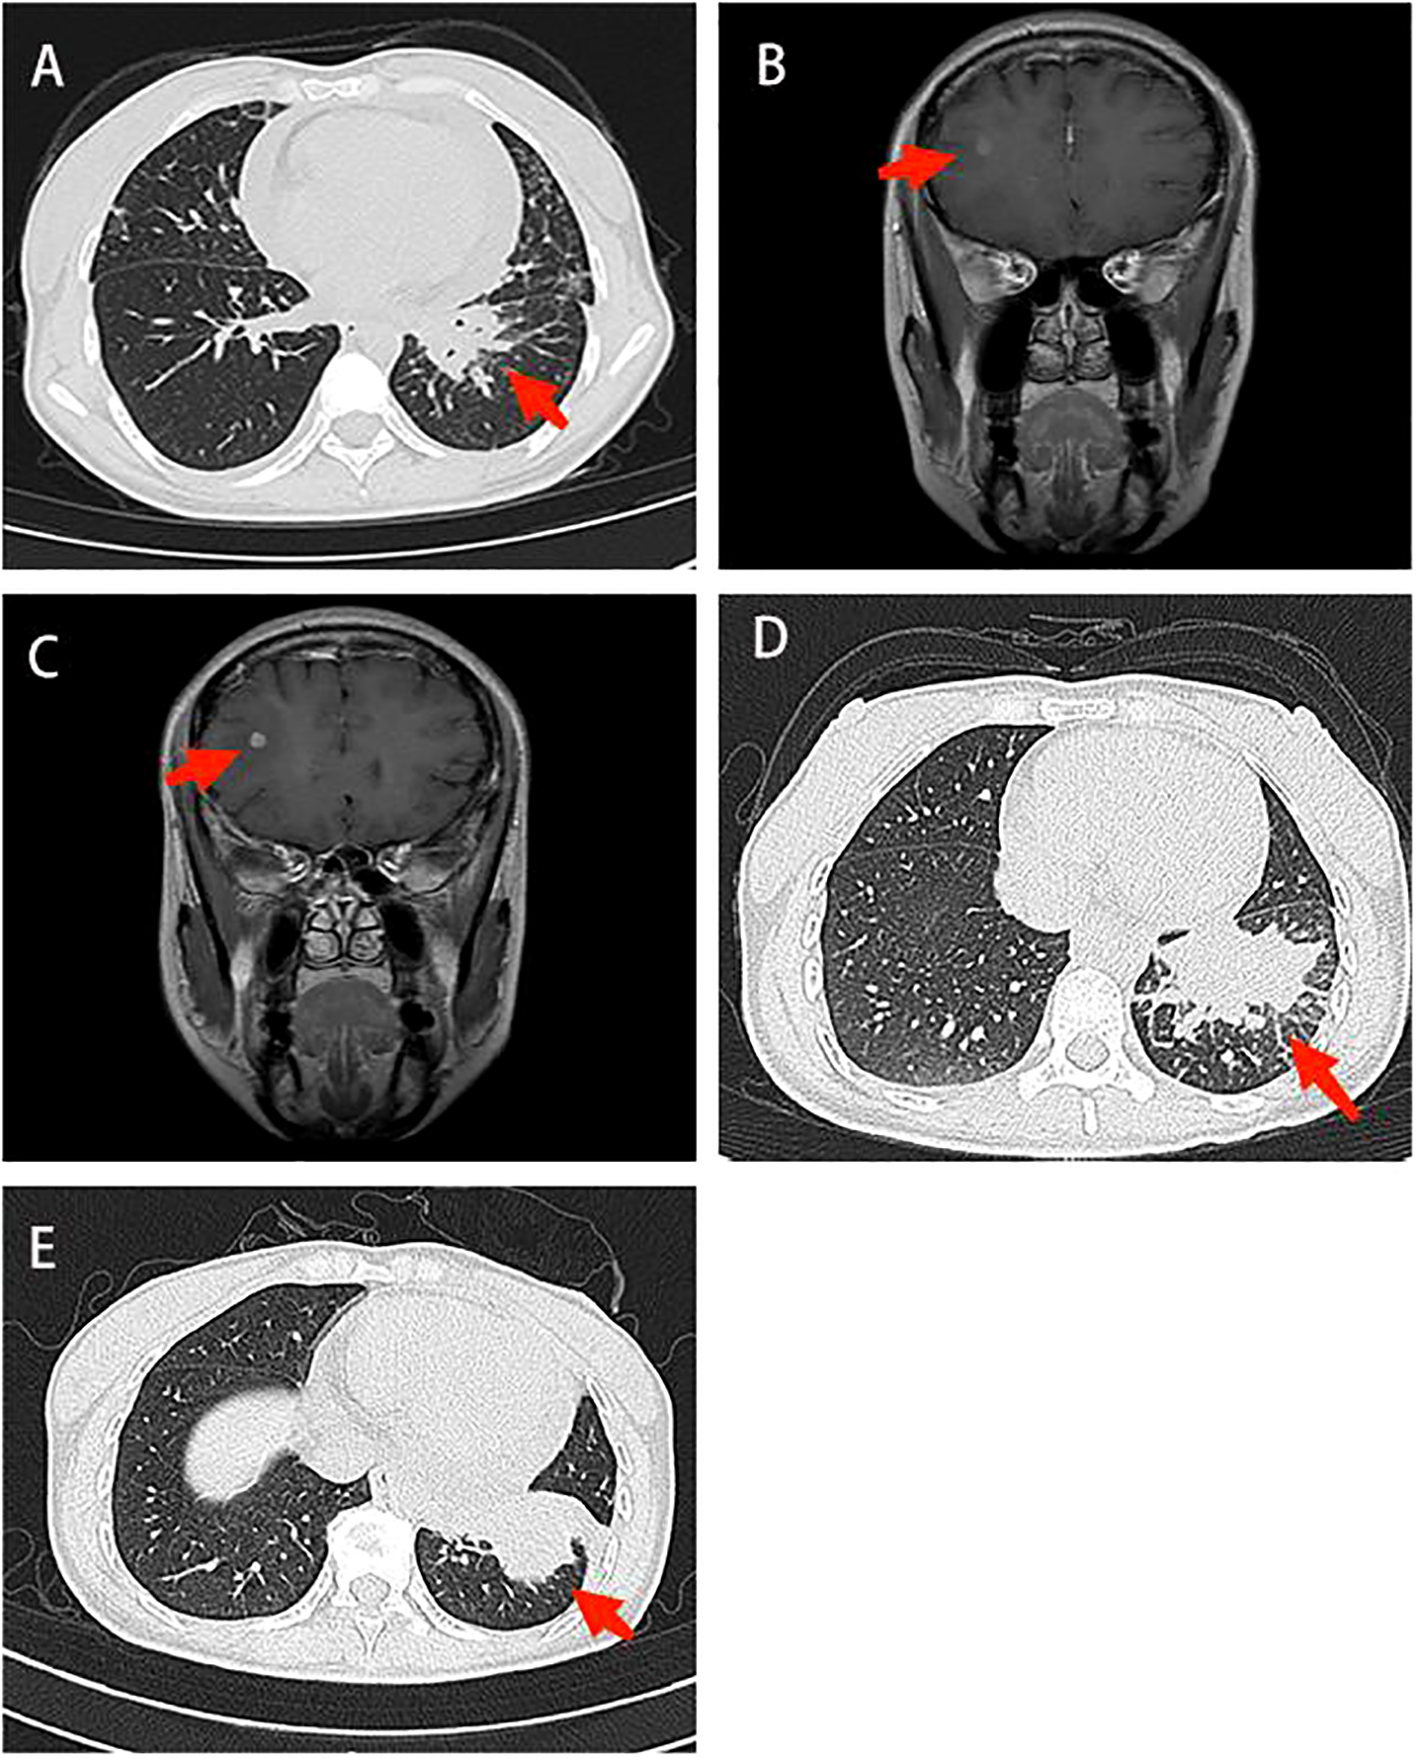

Figure 1

Imaging in diagnosis and treatment. (A) Chest CT: There was a mass shadow in the basal segment of the left lower lobe (B) Contrast-enhanced brain MRI: The right frontal lobe and basal ganglia were enhanced, and the possibility of metastasis was considered (C) Contrast-enhanced brain MRI: The enhancement foci in the right frontal lobe was enlarged compared to the anterior radiograph (2022–11–09). (D) Contrast-enhanced chest CT: The lung cancer in the basal segment of the left lower lobe, significantly enlarged compared to the anterior radiograph (2023–06–07). (E) Chest CT: Lung cancer in the left lower lobe associated with obstructive inflammation, shrank compared to the anterior radiograph (2023–07–14). CT, computed tomography; MRI, magnetic resonance imaging.

On September 4, 2020, a 33-year-old Chinese woman visited our department due to chest tightness and shortness of breath after activity. She had no profession. She never smoked or drank, and there was no special family or personal history. However, elevated carcinoembryonic antigen and carbohydrate antigen were detected, and chest high-resolution computed tomography (CT) suggested a mass shadow in the basal segment of the left lower lobe accompanied by scattered small nodules in the left lung (Figure 1A). Adenocarcinoma cells were found on both in pericardial and pleural effusion smears (Figures 2A, B). The pathological result of bronchoscopy was adenocarcinoma (basal segment of the left lower lobe), and metastatic adenocarcinoma was seen in the 4R group lymph node puncture (Figure 2C). The results of gene detection were EGFR exon 19 mutation and Tumor protein p53 (TP53) mutation. The patient was finally diagnosed with”left lung adenocarcinoma (T3N3M1a IVA stage, EGFR exon 19 mutation and TP53 mutation)”. After excluding the contraindications of chemotherapy, Icotinib combined with pemetrexed and nedaplatin were administered as first-line therapy. On February 1, 2021, the curative effect was evaluated as stable disease (SD). Icotinib and pemetrexed were adopted to maintain chemotherapy for 13 times, and then icotinib was used alone for targeted therapy.

On April 14, 2022, Contrast-enhanced brain magnetic resonance imaging (MRI) revealed an enhanced lesion in the right frontal lobe and basal ganglia (Figure 1B). Combined with the clinical presentation, the possibility of metastatic tumors was considered. Therefore, the physician changed the treatment from icotinib to osimertinib as second-line therapy. At the same time, the patient received 6MV X-ray D95 pGTV 32.5Gy/5F SBRT radiotherapy to the metastatic tumor area in the right frontal lobe and basal ganglia for a total of 5 times from May 30, 2022. On January 6, 2023, the contrast-enhanced brain MRI showed an enlarged enhanced lesion in the right frontal lobe compared with the previous image (2022–11–09) (Figure 1C). Therefore, on January 12, 2023, on the basis of Osimertinib, bevacizumab was given intravenously 5 times.

On July 14, 2023, Contrast-enhanced chest CT suggested lung cancer in the basal segment of the left lower lobe, and the cancer foci was enlarged compared with the previous image (2023–06–07) (Figure 1D). At the same time, neuron-specific enolase (NSE) and squamous carcinoma-associated antigen both elevated by 93.9 ng/mL and 23.5 ng/mL, respectively. CT-guided lung puncture biopsy was performed on July 14, 2023, and the pathology combined with immunohistochemical staining report were consistent with SCLC (Figure 2D). A panel figure with the main immunohistochemical findings of the primary tumor and the progressive tumor was in Figure 3. At the same time, the gene detection was EFGR (+). The patient’s tumor pathology had changed. Thus, the diagnosis was as follows: 1. Malignant tumor of the left lung (rT3N3Mx SCLC, EGFR mutation-positive); 2. Left lung adenocarcinoma (T3N3M1a IVA stage, with metastasis to the pleura, pericardium, and brain, EGFR exon 19 mutation, TP53 mutation). The treatment was changed to cisplatin and etoposide (EP) chemotherapy regime from July 26, 2023.

On September 1, 2023, the patient began to experience chest tightness and chest pain discomfort without any obvious inducement and the symptoms were more severe after activity. A color ultrasound examination suggested a large amount of pericardial effusion (with mild filling signs). Emergency pericardial puncture and tube placement were performed. On September 6, 2023, the pathology report showed adenocarcinoma cells in the pericardial effusion smear (Figure 2E). On September 7, 2023, The chest high-resolution CT scan suggested lung cancer in the lower lobe of the left lung with obstructive inflammation, the cancer foci was smaller than in the previous image (2023–07–14) (Figure 1E). On the morning of September 7, 2023, the patient began to experience mental confusion and sleepiness, which later turned into irritability and restlessness. An emergency brain CT scan showed no significant acute symptoms. After a consultation with a neurologist, lung cancer and brain metastases were considered. As the prognosis was poor, the patient chose to be discharged automatically and transferred to a local hospital for further treatment. The patient eventually died of multiple tumor metastases and severe complications. The treatment timeline of the patient was presented in Figure 4.